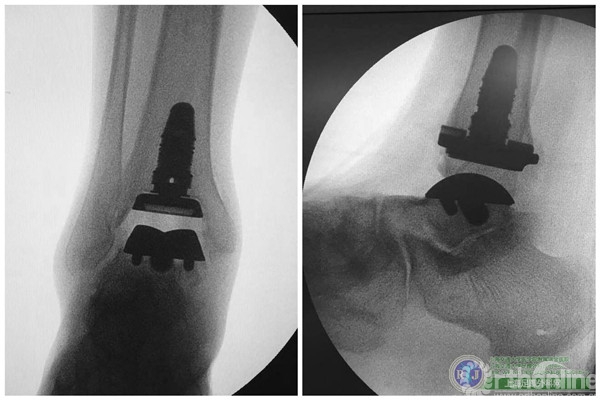

上海瑞金医院骨科足踝外科团队于2015年10月28日上午成功对该患者实施了第三代全踝关节假体(INBONE® II. Wright.)置换手术,手术过程非常顺利。手术中首先清理踝关节内外侧炎性组织及骨赘,将患足置于专门的定制支架中,在透视下反复调整足踝及导针位置,力求最高精确度。在截骨导板的定位下进行踝关节胫骨及距骨的截骨,试样假体大小,置入合适匹配的踝关节假体及垫片完成全踝关节假体的置换,全程手术时间90分钟。完成的全踝关节假体置换位置精确,假体设计稳定牢固,踝关节内外侧软组织平衡,达到了预期的效果。术后患者恢复良好,手术取得圆满成功。患者在休养五周左右以后可以下地行走,去除踝关节炎疼痛畸形的同时能够保留踝关节的活动度,为生活和工作提供极大便利。